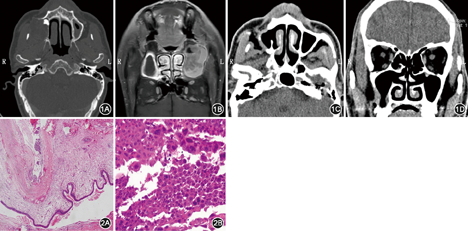

患者男,59岁,因体检发现右侧上颌窦囊肿伴右侧鼻旁肿胀3个月于2015年9月入院。查体:右侧鼻旁见1.0 cm×1.0 cm局限性隆起,触痛阳性,右侧中切牙、侧切牙牙根上方黏膜隆起,牙齿无明显松动和移位,牙弓形态正常。影像学检查见图1,其中增强CT(图1A)示右侧上颌窦、上牙槽骨、上颌骨右侧7.5 cm×8.5 cm等密度影,CT值约-13~3 Hu,局部骨质破坏、不连续。增强MRI(图1B)示右侧上颌窦窦壁形态不规则,窦腔扩大,呈膨胀性改变,窦腔内见不均等信号及稍高信号影,边缘呈环形轻度强化。入院诊断:右侧上颌骨囊肿,入院后第4天全麻下行鼻内镜联合唇龈入路右侧上颌骨囊肿切除术。术中切开、分离唇龈黏膜及黏膜下组织至上颌骨囊肿表面,囊肿呈淡黄色,上颌窦前壁部分骨质缺损,切开囊肿前壁后见囊内大量淡黄色黏稠液体,沿囊壁向上颌窦内分离,完全摘除囊肿,于囊肿内侧近上颌窦前下方见一游离牙,部分嵌顿于上颌骨内,周围囊壁包绕,完整切除该游离牙,在鼻内镜下行下鼻道造瘘,于中鼻道开放上颌窦自然口,缝合唇龈切口,纳吸棉填塞鼻腔。术后组织病理学检查(图2):右侧上颌窦含牙囊肿,局部囊壁鳞状上皮呈重度不典型增生/原位癌。术后于吉林大学口腔医院病理会诊同意该诊断。病理回报后向患者建议进一步行颌骨部分切除及放化疗[1],患者拒绝。术后切口愈合良好,术后1个月、3个月、6个月、1年行鼻内镜检查,均见上颌窦腔内黏膜光滑。术后6个月行鼻窦CT检查示右侧上颌窦腔内未见异常密度影,术后1年再次行鼻窦CT检查未见肿物复发(图1C、图1D)。